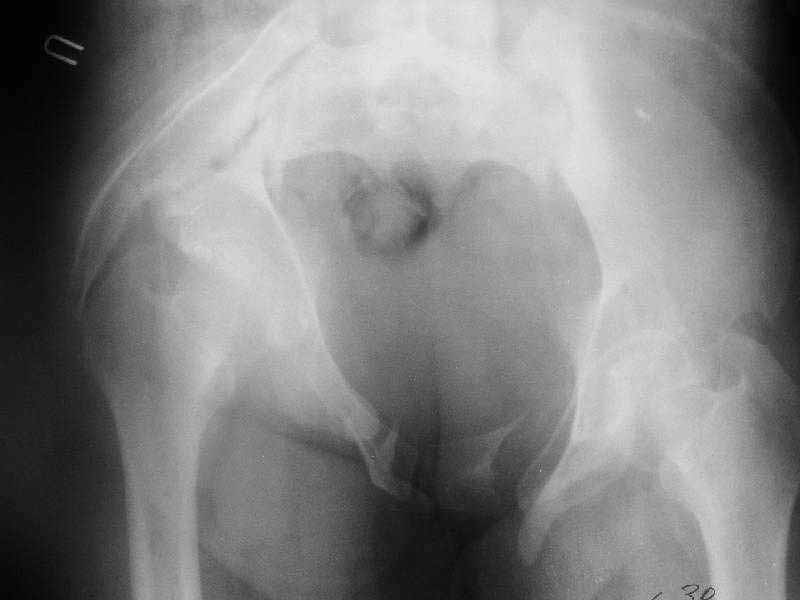

A female 27 years old admitted to our unit. Injured 18 month ago in a car accident. Initially the pelvis was fixed by anterior frame. 1 month later hardware was removed because of pin tract infection, and walk with cruches allowed. Also reptroperitoneal haematoma got infected.

Now there is shortening ~5 cm, no walking aids, of course obvious limp. No signs of infection neither clinically nor in lab tests. Which is optimal management for now? Only to move down the acetabulum (by which approach?), or full reduction of anterior and posterior aspects, acutely or gradually?